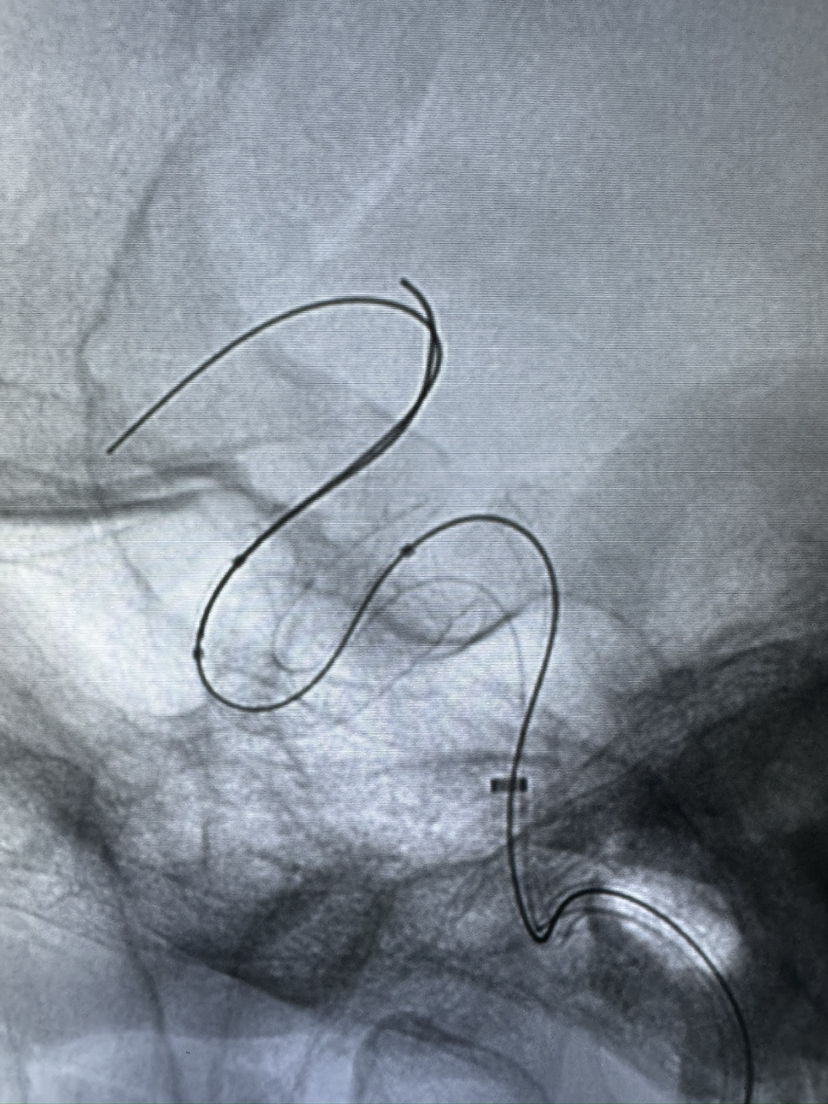

Lattice 支架治疗眼动脉动脉瘤,Scepter c 球囊后扩辅助海绵窦段支架打开